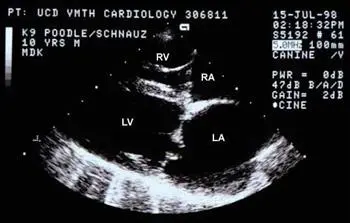

고주파 음파를 이용해 반려동물의 심장 구조와 기능을 실시간으로 확인하는 진단 도구입니다.

심장의 크기, 모양, 4개의 심실, 심장 판막, 심낭 등 심장 안팎의 상태를 세밀하게 평가할 수 있습니다.

또한 컬러 도플러와 스펙트럼 도플러 기법을 활용해 혈액의 흐름을 분석하여, 심장 기능 이상 여부를 비침습적으로 진단할 수 있습니다.

심장초음파 (출처: VIN)